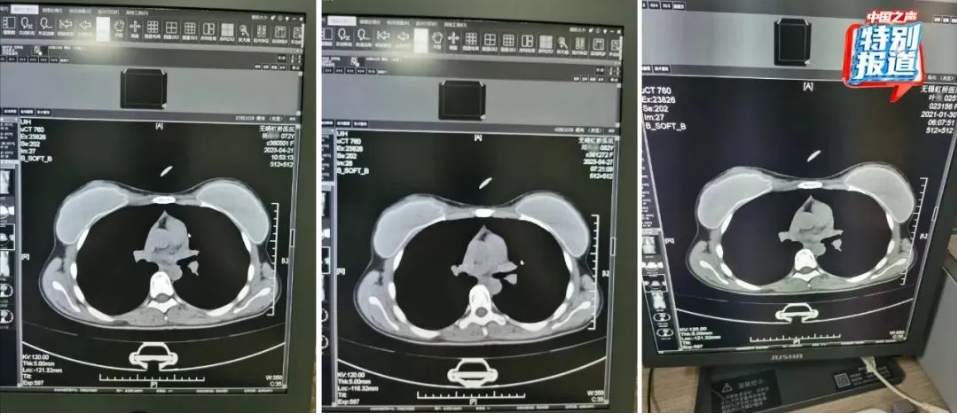

72歲的楊某某、62歲的邱某某與25歲的葉某,三人的片子幾乎一模一樣。

這些病歷全都由醫(yī)院體檢中心陳醫(yī)生完成,而這名醫(yī)生并沒有操作放射影像科CT、核磁共振儀的權(quán)限。放射影像科的醫(yī)生懷疑醫(yī)院涉嫌偽造病歷,騙取醫(yī)療保險。今年3月,他將沒有影像號的病歷拍照留證,向醫(yī)院上級管理部門實名舉報。